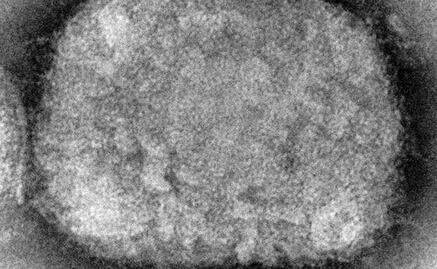

Estocolmo.- Las autoridades sanitarias suecas anunciaron la detección de un primer caso de viruela del mono en el país, tras la aparición de personas en Europa y América del Norte contagiadas de esta enfermedad habitualmente endémica en África.

"Un caso de viruela del mono fue confirmado en una persona en la región de Estocolmo", indicó la Agencia sueca de Salud Pública en un comunicado.

Esta enfermedad tiene como síntomas principales fiebre, dolor de cabeza, dolores musculares, dolor de espalda, ganglios linfáticos inflamados, escalofríos y fatiga. También pueden aparecer erupciones cutáneas, especialmente en la cara, y expandirse a otras partes del cuerpo.

Varias decenas de casos sospechosos o confirmados de viruela del mono se detectaron desde principios de mayo en Europa y América del Norte, lo que hace temer un inicio de propagación de esta enfermedad.